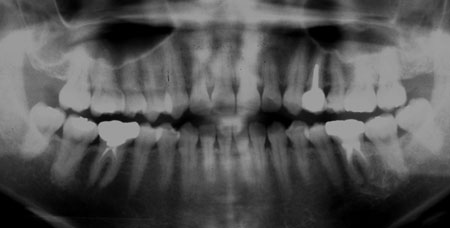

←母親 19歳時のレントゲン写真